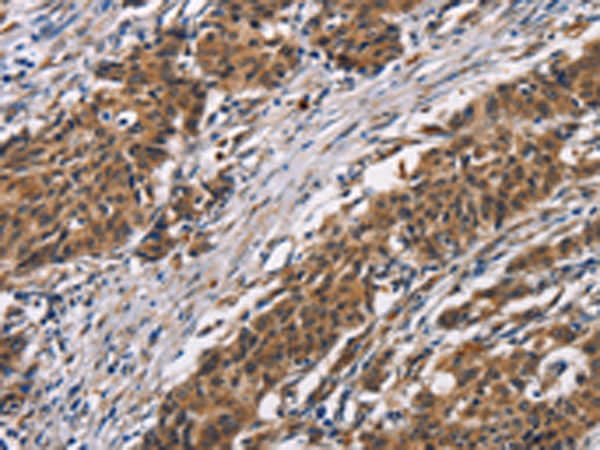

分类: 科研抗体货号: P04704别名: ASB; G4S; MPS6应用: WB,IHC反应种属: Human